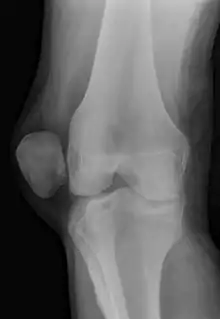

X-ray and MRI after luxation of the patella. There is a fragment and bone bruise at the medial surface of the patella and in the corresponding surface of the lateral condyle of the femur. The medial retinaculum of the patella is disrupted.